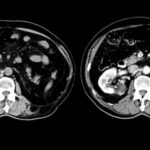

Se trabajó bajo un diseño no experimental, lo que significa que no hubo manipulación de variables, bajo un enfoque horizontal retrospectivo, descriptivo y observacional, donde se empleó la tomografía computada como método diagnóstico principal para el diagnóstico de lesiones quísticas renales. Se utilizó el tomógrafo PHILIPS ACCESS CT (Anexos 13, 14 y 15), emitiendo 16/32 cortes, realizado por médicos especialistas en diagnóstico por imágenes, siguiendo la clasificación Bosniak para categorizar cada uno de los 523 quistes estudiados y poder distinguir por medio del uso de contrastes si correspondían a quistes simples ubicados en la categoría I o a quistes complicados o malignos, los cuales se ubican en las categorías III y IV de Bosniak.

- Bosniak I: el 80% de los quistes (418 pacientes) fueron clasificados como Bosniak I, es decir, quistes simples hallados incidentalmente en tomografía computada (TC) y sin necesidad de seguimiento adicional. De estos, 268 pacientes eran de sexo masculino y 150 de sexo femenino (Anexos 17 y 18).

- Bosniak II: el 10% de los quistes (55 pacientes) fueron catalogados como Bosniak II, correspondientes a quistes benignos. Esta categoría incluyó a 36 pacientes de sexo masculino y 19 de sexo femenino (Anexos 19 y 20).